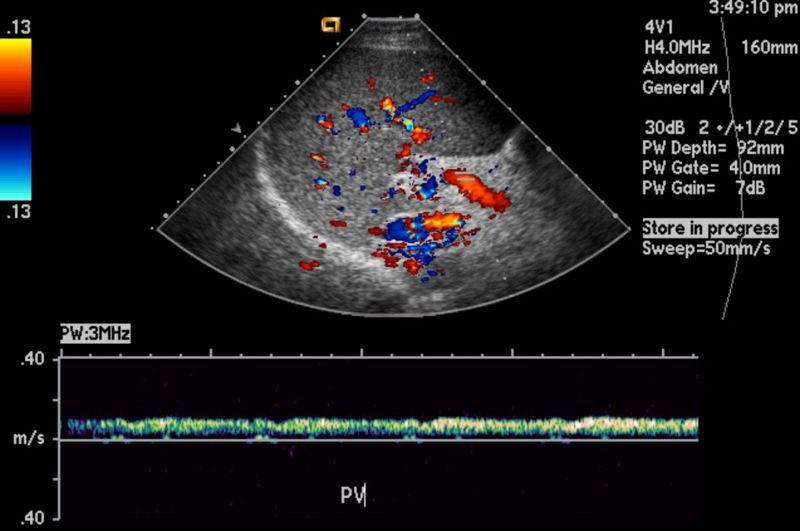

Evaluación del Flujo Sanguíneo Cerebral

Además de visualizar la estructura neurológica, el ultrasonido obstétrico permite evaluar el flujo sanguíneo cerebral. Un suministro sanguíneo adecuado es esencial para el desarrollo cerebral óptimo, y esta tecnología nos permite monitorear esta función vital. Cualquier irregularidad en el flujo sanguíneo puede ser una señal de alerta temprana para los profesionales médicos.